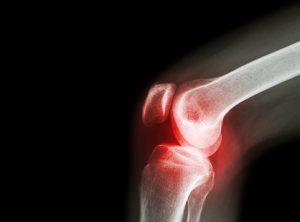

Imaging testing may also be done to assess the possible joint damage done by the infection and may include an x-ray, MRI, CT scan, or nuclear scan.

- Radiograph: An x-ray that can be useful in initial stages of the disease to show joint effusion.